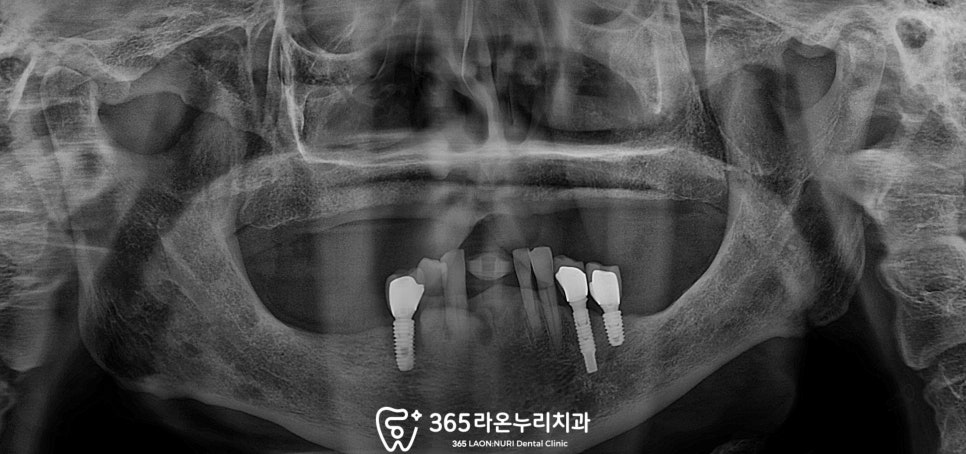

남촌동 치과 에서 엑스레이를 확인한 결과

상악은 전체 틀니를 사용 중이고

하악은 대구치는 모두 상실되고

전치부까지 상실된 케이스였습니다.